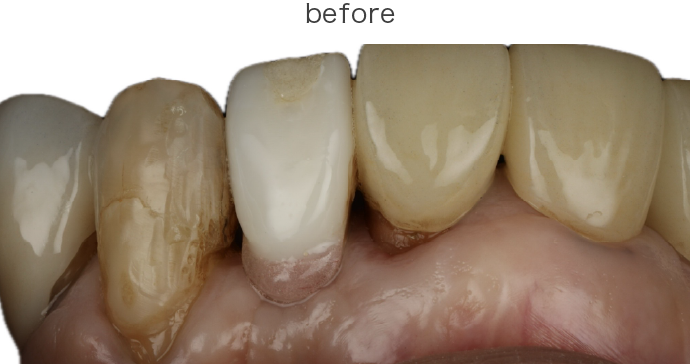

歯を失ってしまった時、見た目だけでなく噛み合わせや食生活、さらには全身の健康にも影響が及ぶことがあります。そのため、当院では「抜歯ありき」ではなく、まずは「抜かずに残せるかどうか」を精密に診査・診断し、最適な治療プランをご提示することを心がけています。

たとえ「抜歯が必要」と診断された場合でも、状態によっては以下のような処置によって歯を残す可能性があります。

当院では、これらの高度な処置を含め、「残すための最善策」を選択肢としてご提示いたします。

| 治療内容 | 上段 根面被服術(歯茎を上げる手術) |

| 治療費 | 総額 88000円〜 |

| 治療回数 | 1回 |

| リスク | 術部の発赤、腫脹、疼痛、部分的なネクローシス |